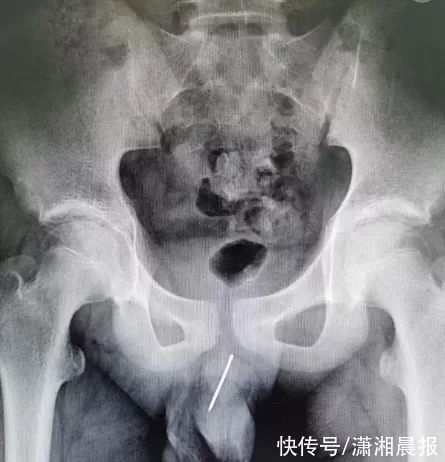

近日,南京市儿童医院泌尿外科接收了一位情况危及的小病人。一位13岁男孩被家长送来急诊,孩子莫名出现了血尿的情况,并伴有疼痛和不适感,但一时找不出原因。

拍片检查后,男孩的片子上显示出一根细长的金属阴影。

经过再三询问后,男孩说出实情,原来一两周前他因好奇将一根缝被子的钢针从尿道塞入,塞进去后孩子立刻感到不适,但已经取不出来,想尿也尿不出来。

接诊医生汪俊介绍,男性的尿道有2个生理弯曲,尖锐的针在身体中可能随着活动引起尿道、直肠、膀胱等其它组织的损伤,医院当即安排了急诊手术。

医生计划通过膀胱镜取出异物,但由于钢针表面非常光滑,异物钳夹取困难。手术中医生们发现,钢针已经位于后尿道,且针尖已经扎进尿道壁组织内。在医生仔细的操作下,最终钢针被顺利取出,取出的大号钢针足有9厘米长,令在场的医护人员大吃一惊。